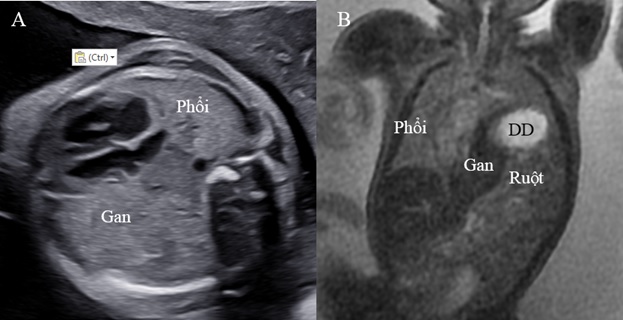

MRI là phương tiện chẩn đoán hình ảnh cao cấp giúp đánh giá thể tích phổi bên thoát vị và cả bên đối diện chính xác hơn siêu âm. Chụp cộng hưởng từ cũng cho phép đánh giá tốt về thoát vị gan, tỷ lệ gan trong lồng ngực vì độ tương phản của phổi và gan có sự khác biệt rõ trên MRI chứ không tương tự như trên siêu âm thang xám. Nên hiện nay ở một số trung tâm tiền sản, MRI được chỉ định thường quy cho CDH để giúp chẩn đoán và đánh giá tiên lượng chính xác hơn.

Với CDH bên trái, gan có thoát vị lên lồng ngực là một yếu tố dự báo độc lập bên cạnh kích thước phổi (như o/e LHR). Về mặt lý thuyết, có thể dùng siêu âm đánh giá phần gan trong lồng ngực, Nhưng trên siêu âm, độ hồi âm của gan rất giống với phổi nên sự đánh giá chính xác phần gan trong lồng ngực có phần hạn chế. MRI giúp đánh giá chính xác hơn vì tín hiệu của gan và phổi khác biệt rõ. Thể tích phổi toàn phần quan sát/mong đợi trên MRI (TLV) được dùng để đánh giá tiên lượng trong trường hợp thoát vị có gan lên.

Hình 6. A: Phản âm của gan và phổi tương tự nhau trên siêu âm 2D. B: Có sự khác biệt tín hiệu của phổi, gan, ruột và dạ dày trên MRI